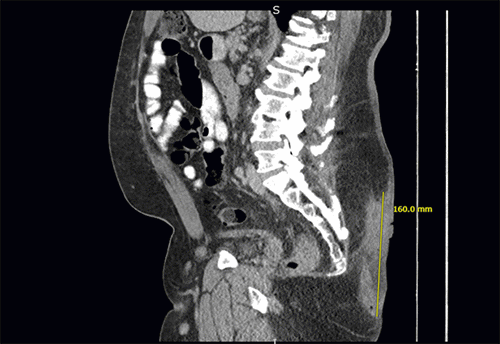

A 60-year-old male presented to an emergency department with symptoms of perianal pain and bleeding. He had a history of abscess drainage in his gluteal cleft over 20 years ago. Despite occasional discomfort and drainage since then, he did not seek medical attention. He works around 60 hours weekly as a truck driver and mainly sits during work. Over the past two weeks, he experienced increasing coccygeal pain with occasional bloody drainage. Upon examination, an 8 cm fungating mass was discovered in his gluteal cleft (Figure 1). A core biopsy confirmed well-differentiated squamous cell carcinoma. No regional lymphadenopathy was observed, and a screening CT scan of his chest, abdomen, and pelvis showed no distant metastatic disease (Figure 2).

Figure 2. Saggital Image From Staging CT Scan. Published with Permission

Note large pilonidal mass with associated soft tissue inflammation measuring 16.0 × 4.5 × 4.0 cm. Inflammatory changes extend to the sacral fascia